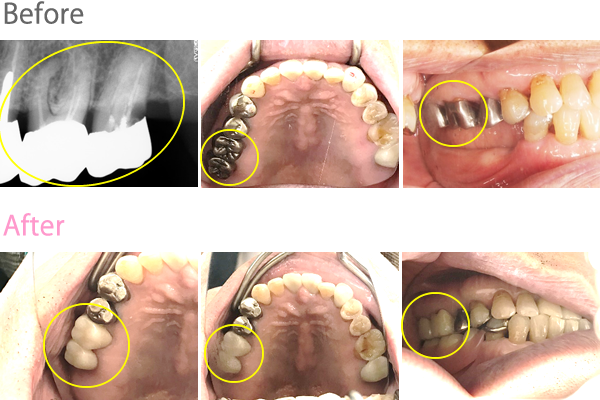

男性Tさん 80代(オールセラミック冠)

主訴

左上の歯茎が腫れて、噛むと痛い

治療内容

左上奥2本が、根の先端で問題を起こし、歯肉が腫れていましたので、根管治療をしました。患者さんは、メタルフリーの治療を希望されましたので、オールセラミック冠を被せました。

所感

根管治療をしたところ、歯肉の腫れは、きれいになくなりました。お口の中には、まだ金属冠がありました。体全体の健康のことを考えると、徐々に金属を取り除いた方が良いことをお話ししました。

オールセラミック冠2本:¥80,000×2本=¥160,000(税別)